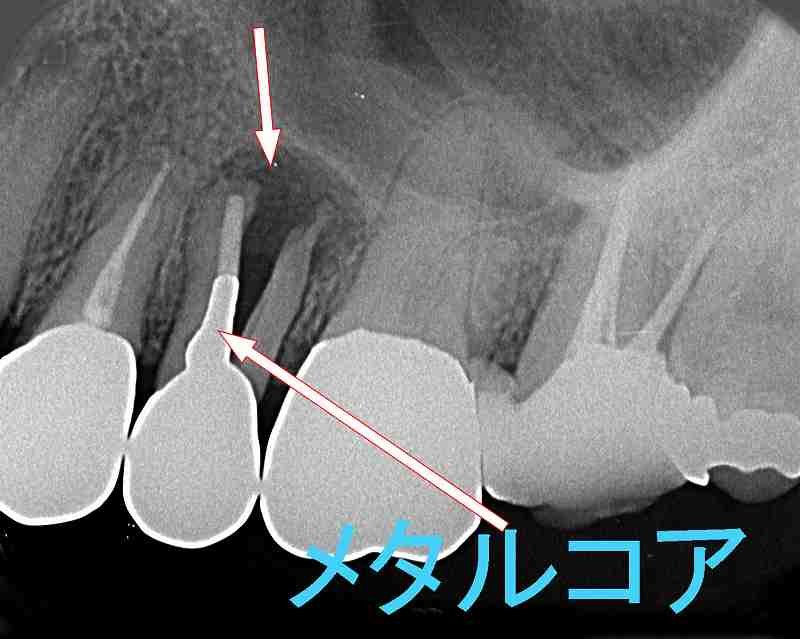

当院は、日本口腔インプラント学会の専門医・指導医が在籍する信頼の歯科医院です。難症例や多数歯のインプラント治療において豊富な実績があり、他院で断られたケースにも対応しています。

特に、サイナスリフトや骨造成といった高度な治療技術を駆使し、患者様一人ひとりの状況に最適な治療法をご提供します。専門的な知識と技術で、複雑な症例にも安心してお任せいただけます。